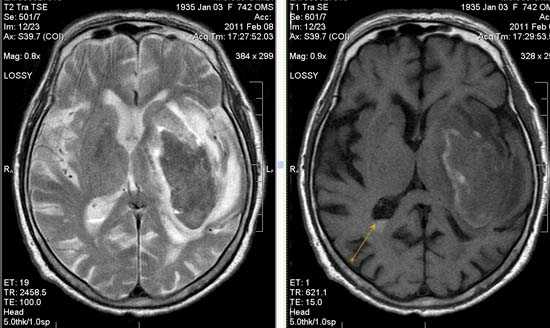

Некоторые инфаркты при дисциркуляторной энцефалопатии протекают бессимптомно. Это «немые» инфаркты, которые, как правило, локализуются в глубоких отделах мозга и диагностируются только при МРТ. Этот случай показывает возможности выявление очага ограниченного ишемического ОНМК базальных ядер слева на фоне хронической ишемии.

Выраженная сосудистая энцефалопатия с наличием множественных очагов хронической ишемии, лакунарных постишемических кист. Программа ДВИ четко показывает фокус острого ОНМК в базальных ядрах справа на фоне лейкодистрофии.

Внутримозговая гематома (граница острой и ранней подострой стадий - 3 суток), осложнившаяся внутрижелудочковым кровоизлиянием.

Внутримозговая гематома, поздний подострый период (14-21 день) с перифокальным отеком вокруг гематомы.

Внутримозговая гематома правой теменной доли. Граница поздней подострой и ранней хронической стадии. В Т2-ВИ виден ободок гемосидерина (стрелка).

Хочется подчеркнуть возможность МРТ в выявлении последствий геморрагического поражения - остается хорошо дифференцируемый по Т2 ободок гемосидерина, недоступный для визуализации при других методах нейровизуализации.

Стрелками показан ободок гемосидерина по периферии постишемической кисты.